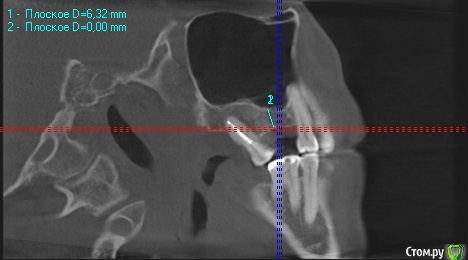

wladdX Опубликовано 27 февраля, 2019 Поделиться Опубликовано 27 февраля, 2019 (изменено) Скриншоты Сколько успел Изменено 27 февраля, 2019 пользователем wladdX Ссылка на комментарий

red_butler Опубликовано 27 февраля, 2019 Поделиться Опубликовано 27 февраля, 2019 соустье нужно посмотреть, но предварительно - не вижу препятствий для проведения открытого синуслифта Ссылка на комментарий

wladdX Опубликовано 27 февраля, 2019 Поделиться Опубликовано 27 февраля, 2019 Похоже, я загрузил скрины другого пациента (на диске записаны 2 исследования), исправляюсь. Ссылка на комментарий

kramer Опубликовано 27 февраля, 2019 Поделиться Опубликовано 27 февраля, 2019 Закрытый синус-лифт + 10 мм имплантат Ссылка на комментарий

red_butler Опубликовано 27 февраля, 2019 Поделиться Опубликовано 27 февраля, 2019 8 мм имплант и закрытый синус без графта Ссылка на комментарий

колесников Опубликовано 3 марта, 2019 Поделиться Опубликовано 3 марта, 2019 У вас речь идёт об одном импланты в области 16. Одиночный короткий Имплант не рекомендуется ни одним из производителей имплантов. Открытый синуслифтинг не показан из за особенностей строения пазухи в этой области,показан закрытый. Так же рекомендовал бы Астра тек,4.5х9. А также:дистализация 17го и имплантация в области 47.. либо удаление 17го,имплантация 17,16,47 Ссылка на комментарий